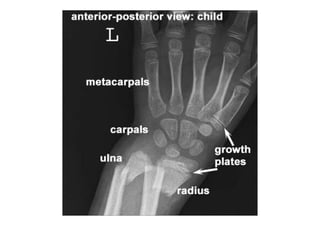

RADIOLOGIA DO

TRAUMA DO ESQUELETO

Referência: http://www.accessexcellence.org/RC/VL/